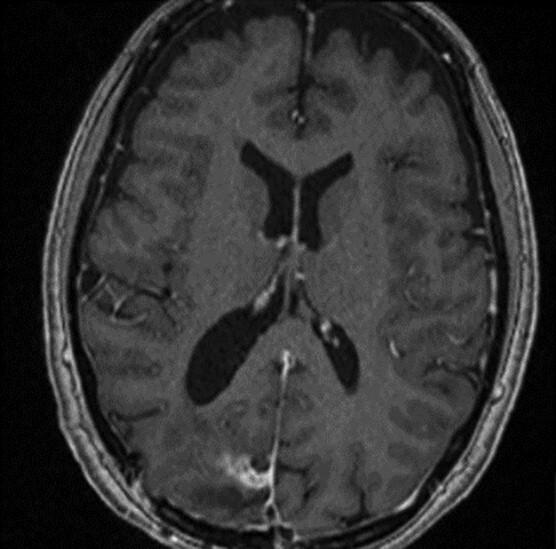

Central nervous system (CNS) infection and neoplasm occur most often independently. Their concomitant presentation has been noted across different CNS tumours but is considered a rare entity. The phenomenon is mostly seen in relation to direct seeding of infection via frontal air sinuses. Here, we present an unusual case of an occipital meningioma associated with intraparenchymal paratumoural abscess formation. It is also the second documented to culture methicillin-susceptible . We then review and surmise the relevant literature of meningioma-associated abscess. We discuss the clinical presentations, aetiology, suspected pathogenesis, management and outcomes reported.

中枢神经系统(CNS)感染和肿瘤大多独立发生。它们同时出现的情况在不同的中枢神经系统肿瘤中均有记载,但被认为是一种罕见现象。这种现象大多与通过额窦的感染直接播散有关。在此,我们报告一例不寻常的枕部脑膜瘤合并脑实质内瘤旁脓肿形成的病例。这也是第二例培养出对甲氧西林敏感……的病例。然后我们回顾并推测了与脑膜瘤相关脓肿的相关文献。我们讨论了所报道的临床表现、病因、疑似发病机制、治疗及结果。